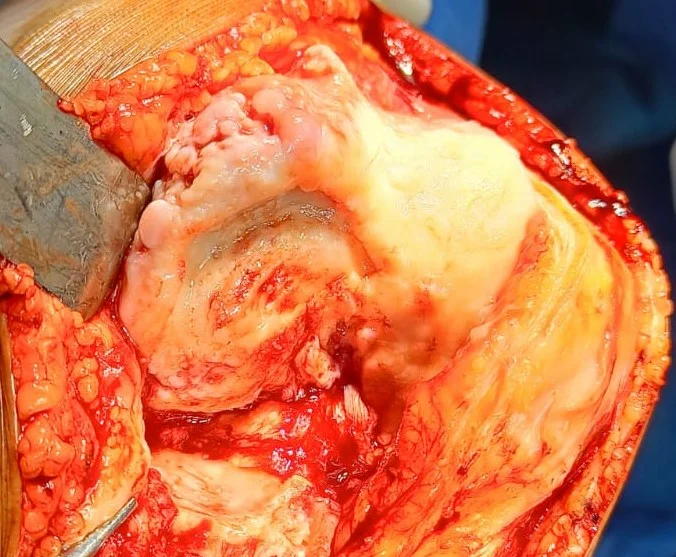

3. Surgery

Usual duration of surgery is 90-100 mins. The surgery principally aims at precise measured

resection of eroded cartilage & bone of knee joint, correction of deformity, appropriate

balancing of soft tissue.